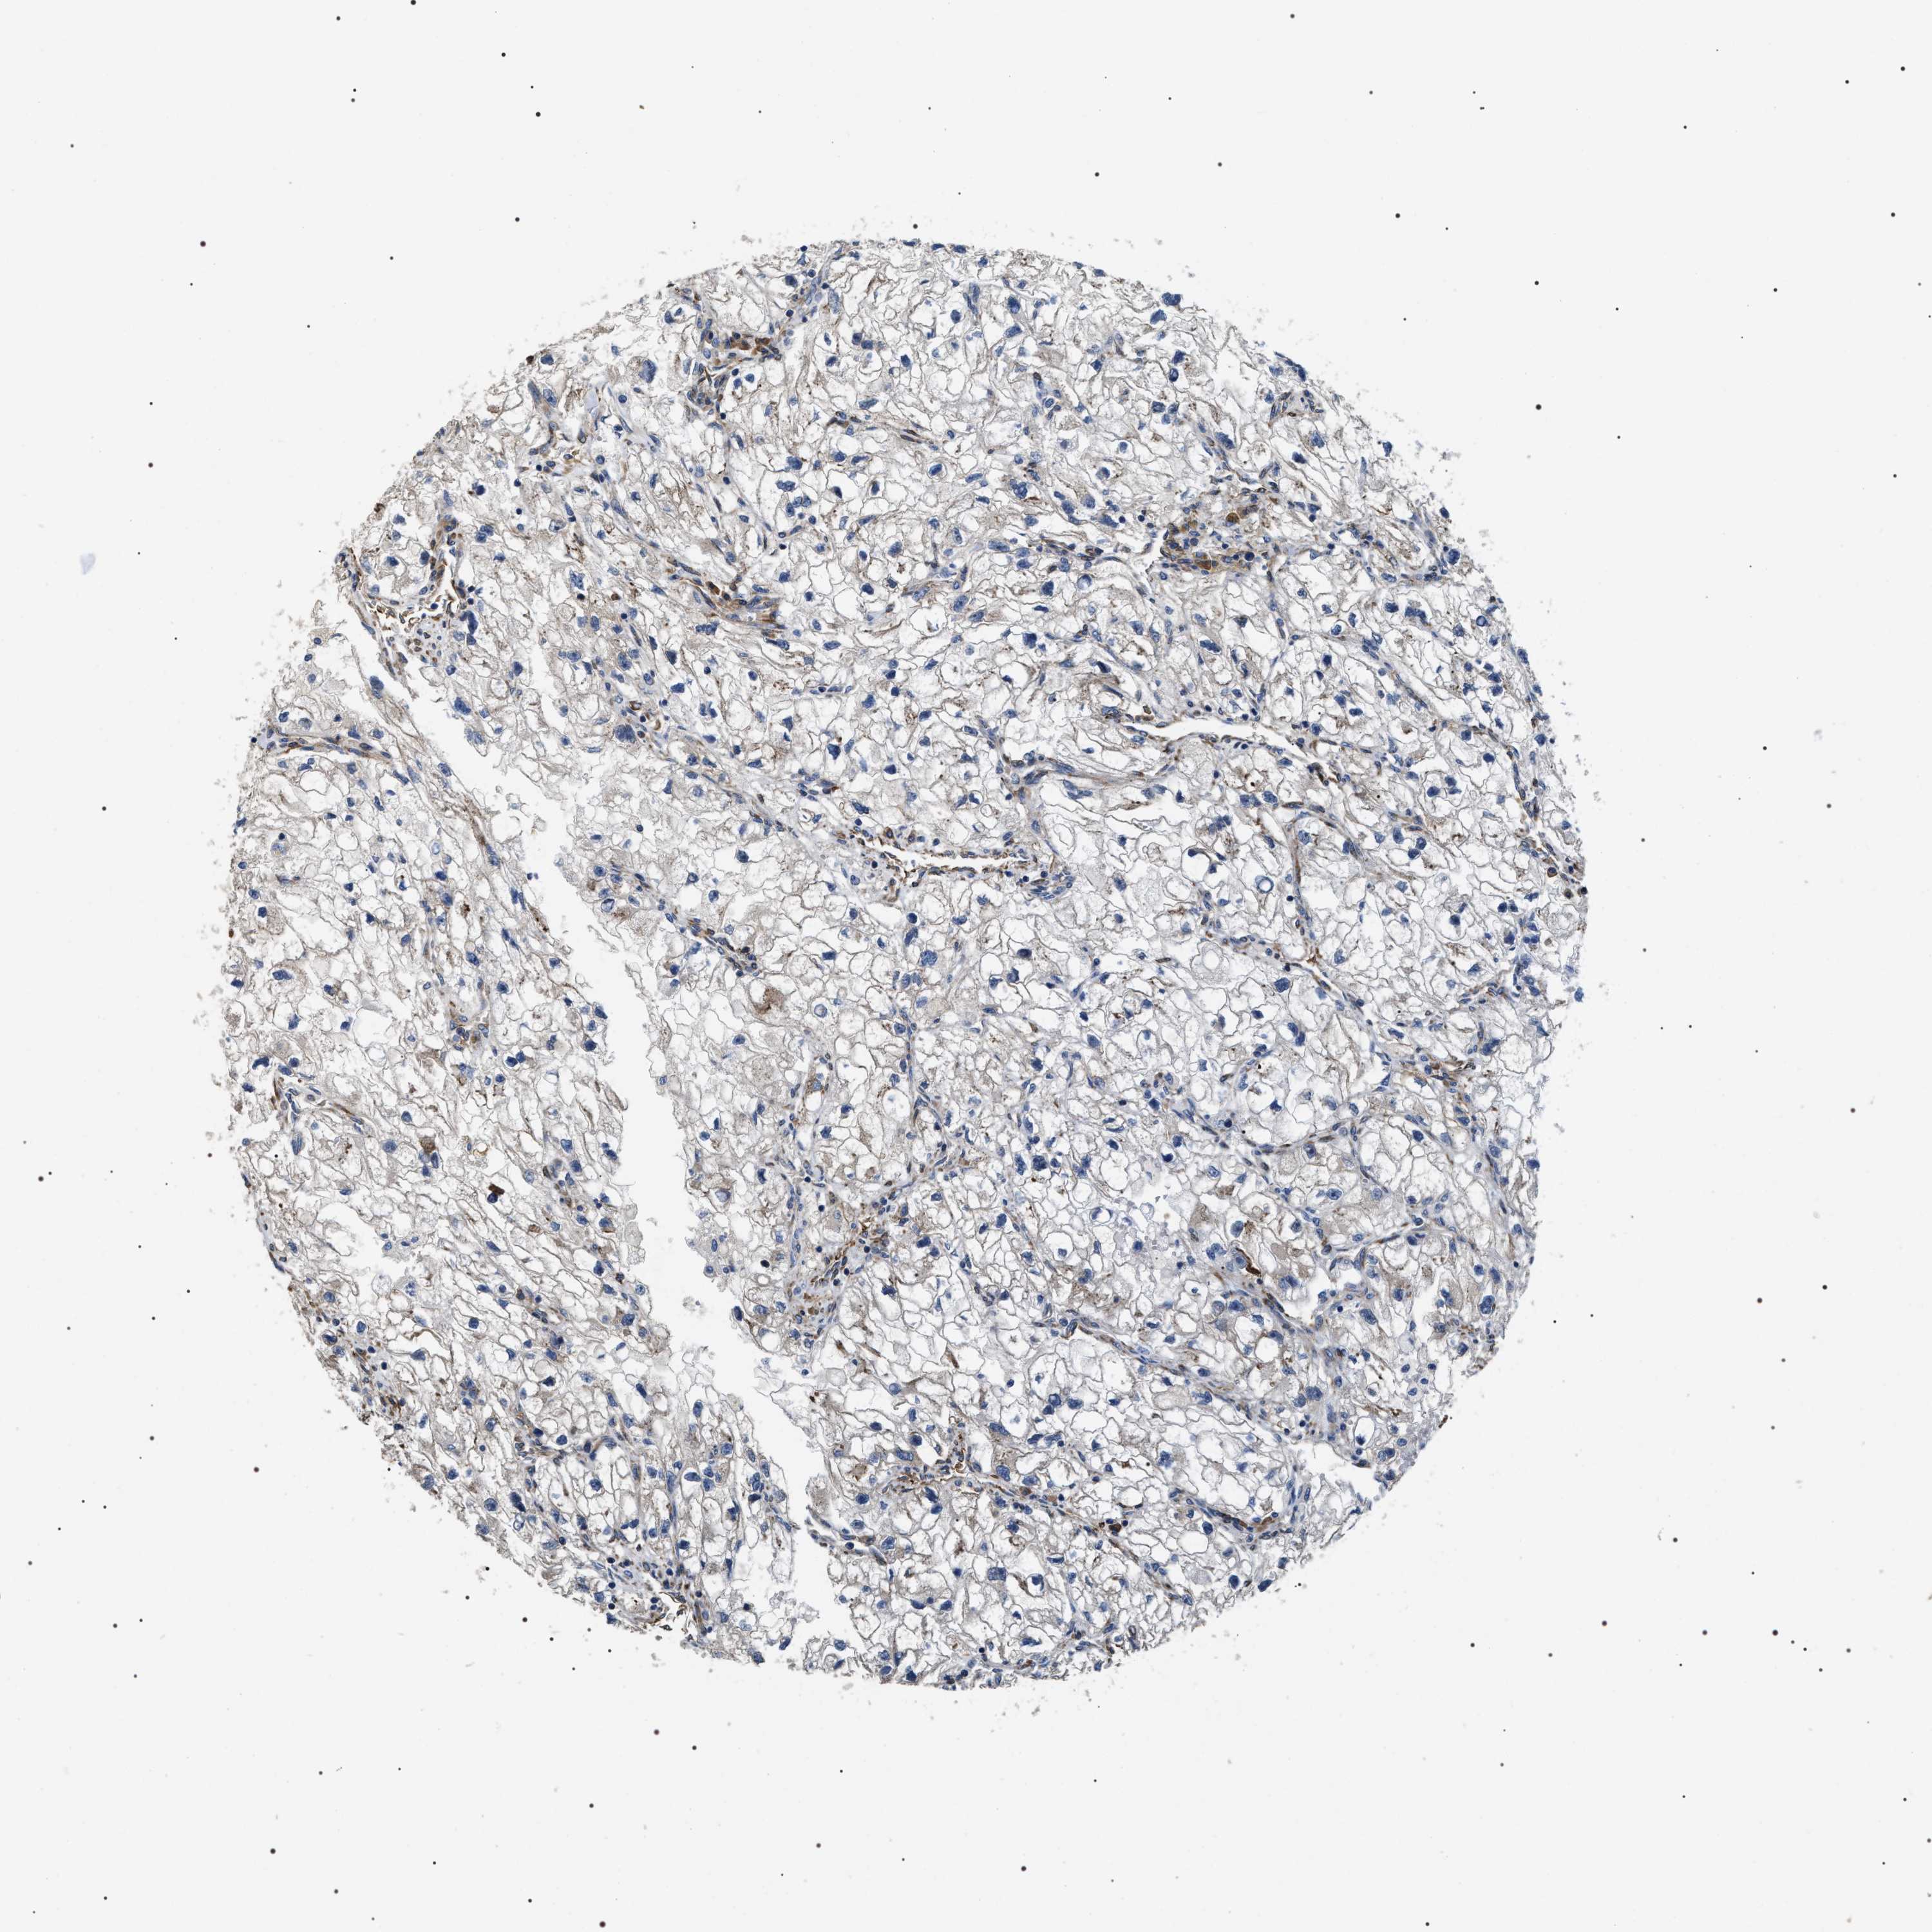

KIDNEY RENAL CLEAR CELL CARCINOMA (VALIDATION) - Interactive survival scatter ploti

The Survival Scatter plot shows the clinical status (i.e. dead or alive) for all individuals in the patient cohort, based on the same data that underlies the corresponding Kaplan-Meier plots. Patients that are alive at last time for follow-up are shown in blue and patients who have died during the study are shown in red.

The x-axis shows the expression levels (FPKM) of the investigated gene in the tumor tissue at the time of diagnosis. The y-axis shows the follow-up time after diagnosis (years). Both axes are complimented with kernel density curves demonstrating the data density over the axes. The top density plot shows the expression levels (FPKM) distribution among dead (red) and alive patients (blue). The right density plot shows the data density of the survived years of dead patients with high and low expression levels respectively, stratified using the cutoff indicated by the vertical dashed line through the Survival Scatter plot. This cutoff is automatically defined based on the FPKM cutoff that minimizes the p-score. The cutoff can be changed by dragging the vertical line or by entering a cutoff value in the square labeled "Current cut-off".

Under the Survival Scatter plot the p-score landscape (black curve; left axis) is shown together with dead median separation (red curve; right axis). Dead median separation is the difference in median mRNA expression between patients who have died with high and low expression, respectively. It is calculated as follows: median FPKM expression of dead patients with high expression - median FPKM expression of dead patients with low expression. This is intended to aid the user in visually exploring custom cutoffs and the associated p-scores and dead median separation.

Individual patient data is displayed and can be filtered by clicking on one or more of the category buttons on the top of the page. Categories describing expression level and patient information include: high, low, alive, dead, female, male and tumor stages. The scale of the x-axis can be toggled between linear and log-scale by clicking on the "x log" button. Mouse-over function shows TCGA ID, patient information and mRNA expression (FPKM) for each patient.

& Survival analysisi

Kaplan-Meier plots summarize results from analysis of correlation between mRNA expression level and patient survival. Patients were divided based on level of expression into one of the two groups "low" (under cut off) or "high" (over cut off). X-axis shows time for survival (years) and y-axis shows the probability of survival, where 1.0 corresponds to 100 percent.

ZC3HAV1L is not prognostic in Kidney Renal Clear Cell Carcinoma (validation)

: 9.84

Average pTPM 14.8

Number of samples 100